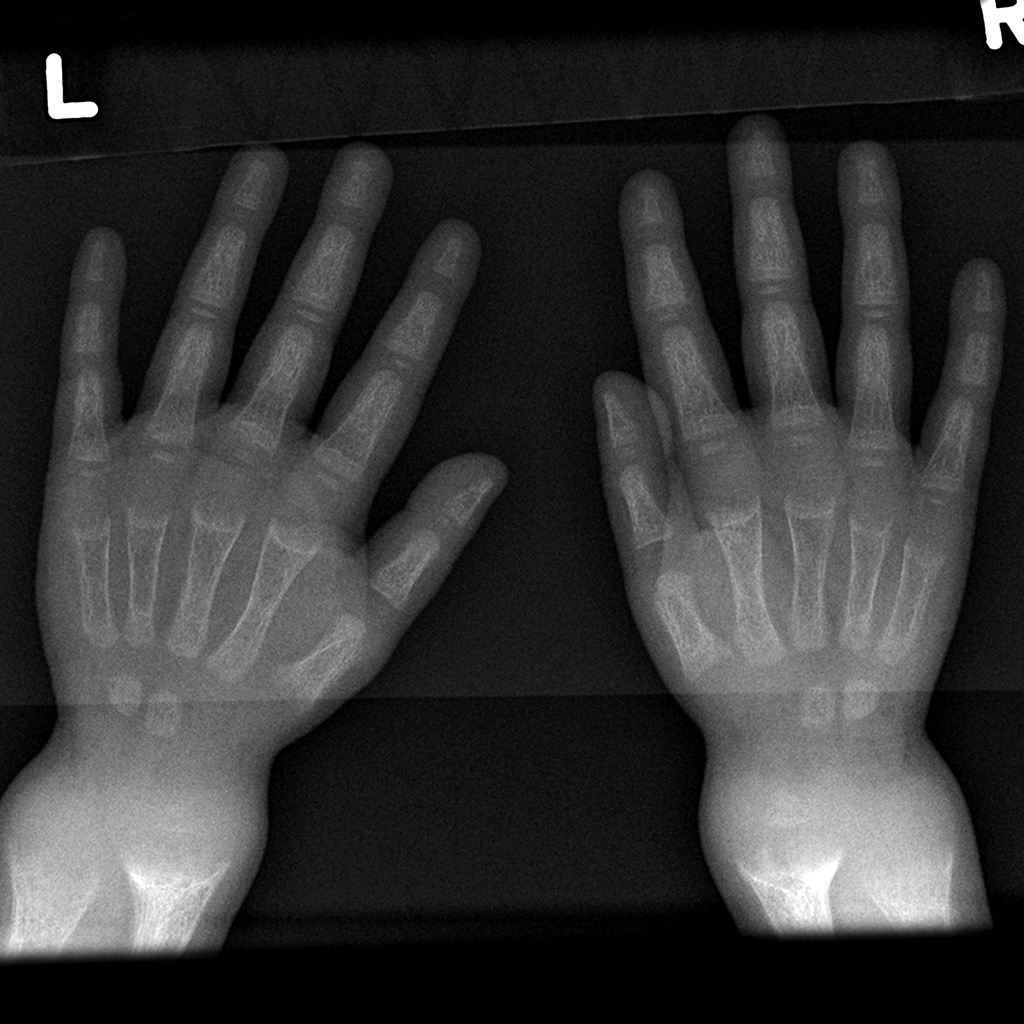

Learning Radiology Lead, poisoning, plumbism, intoxication, ingestion Lead Line X Ray Lead is known to be a highly toxic metal and chronic lead exposure, often asymptomatic, results in increased morbidity. The classic findings of lead lines on radiographs of long bones are rarely seen because most cases of lead poisoning in children are due to exposures to low or moderate. In this post, we'll explore why it is important to use. Lead Line X Ray.

Pediatric Radiology Lead Line X Ray The classic findings of lead lines on radiographs of long bones are rarely seen because most cases of lead poisoning in children are due to exposures to low or moderate. Lead is known to be a highly toxic metal and chronic lead exposure, often asymptomatic, results in increased morbidity. Completion of the equipment room drawing and radiation shielding intake form.. Lead Line X Ray.

Learning Radiology Lead, poisoning, plumbism, intoxication, ingestion Lead Line X Ray The classic findings of lead lines on radiographs of long bones are rarely seen because most cases of lead poisoning in children are due to exposures to low or moderate. Lead is known to be a highly toxic metal and chronic lead exposure, often asymptomatic, results in increased morbidity. In this post, we'll explore why it is important to use. Lead Line X Ray.